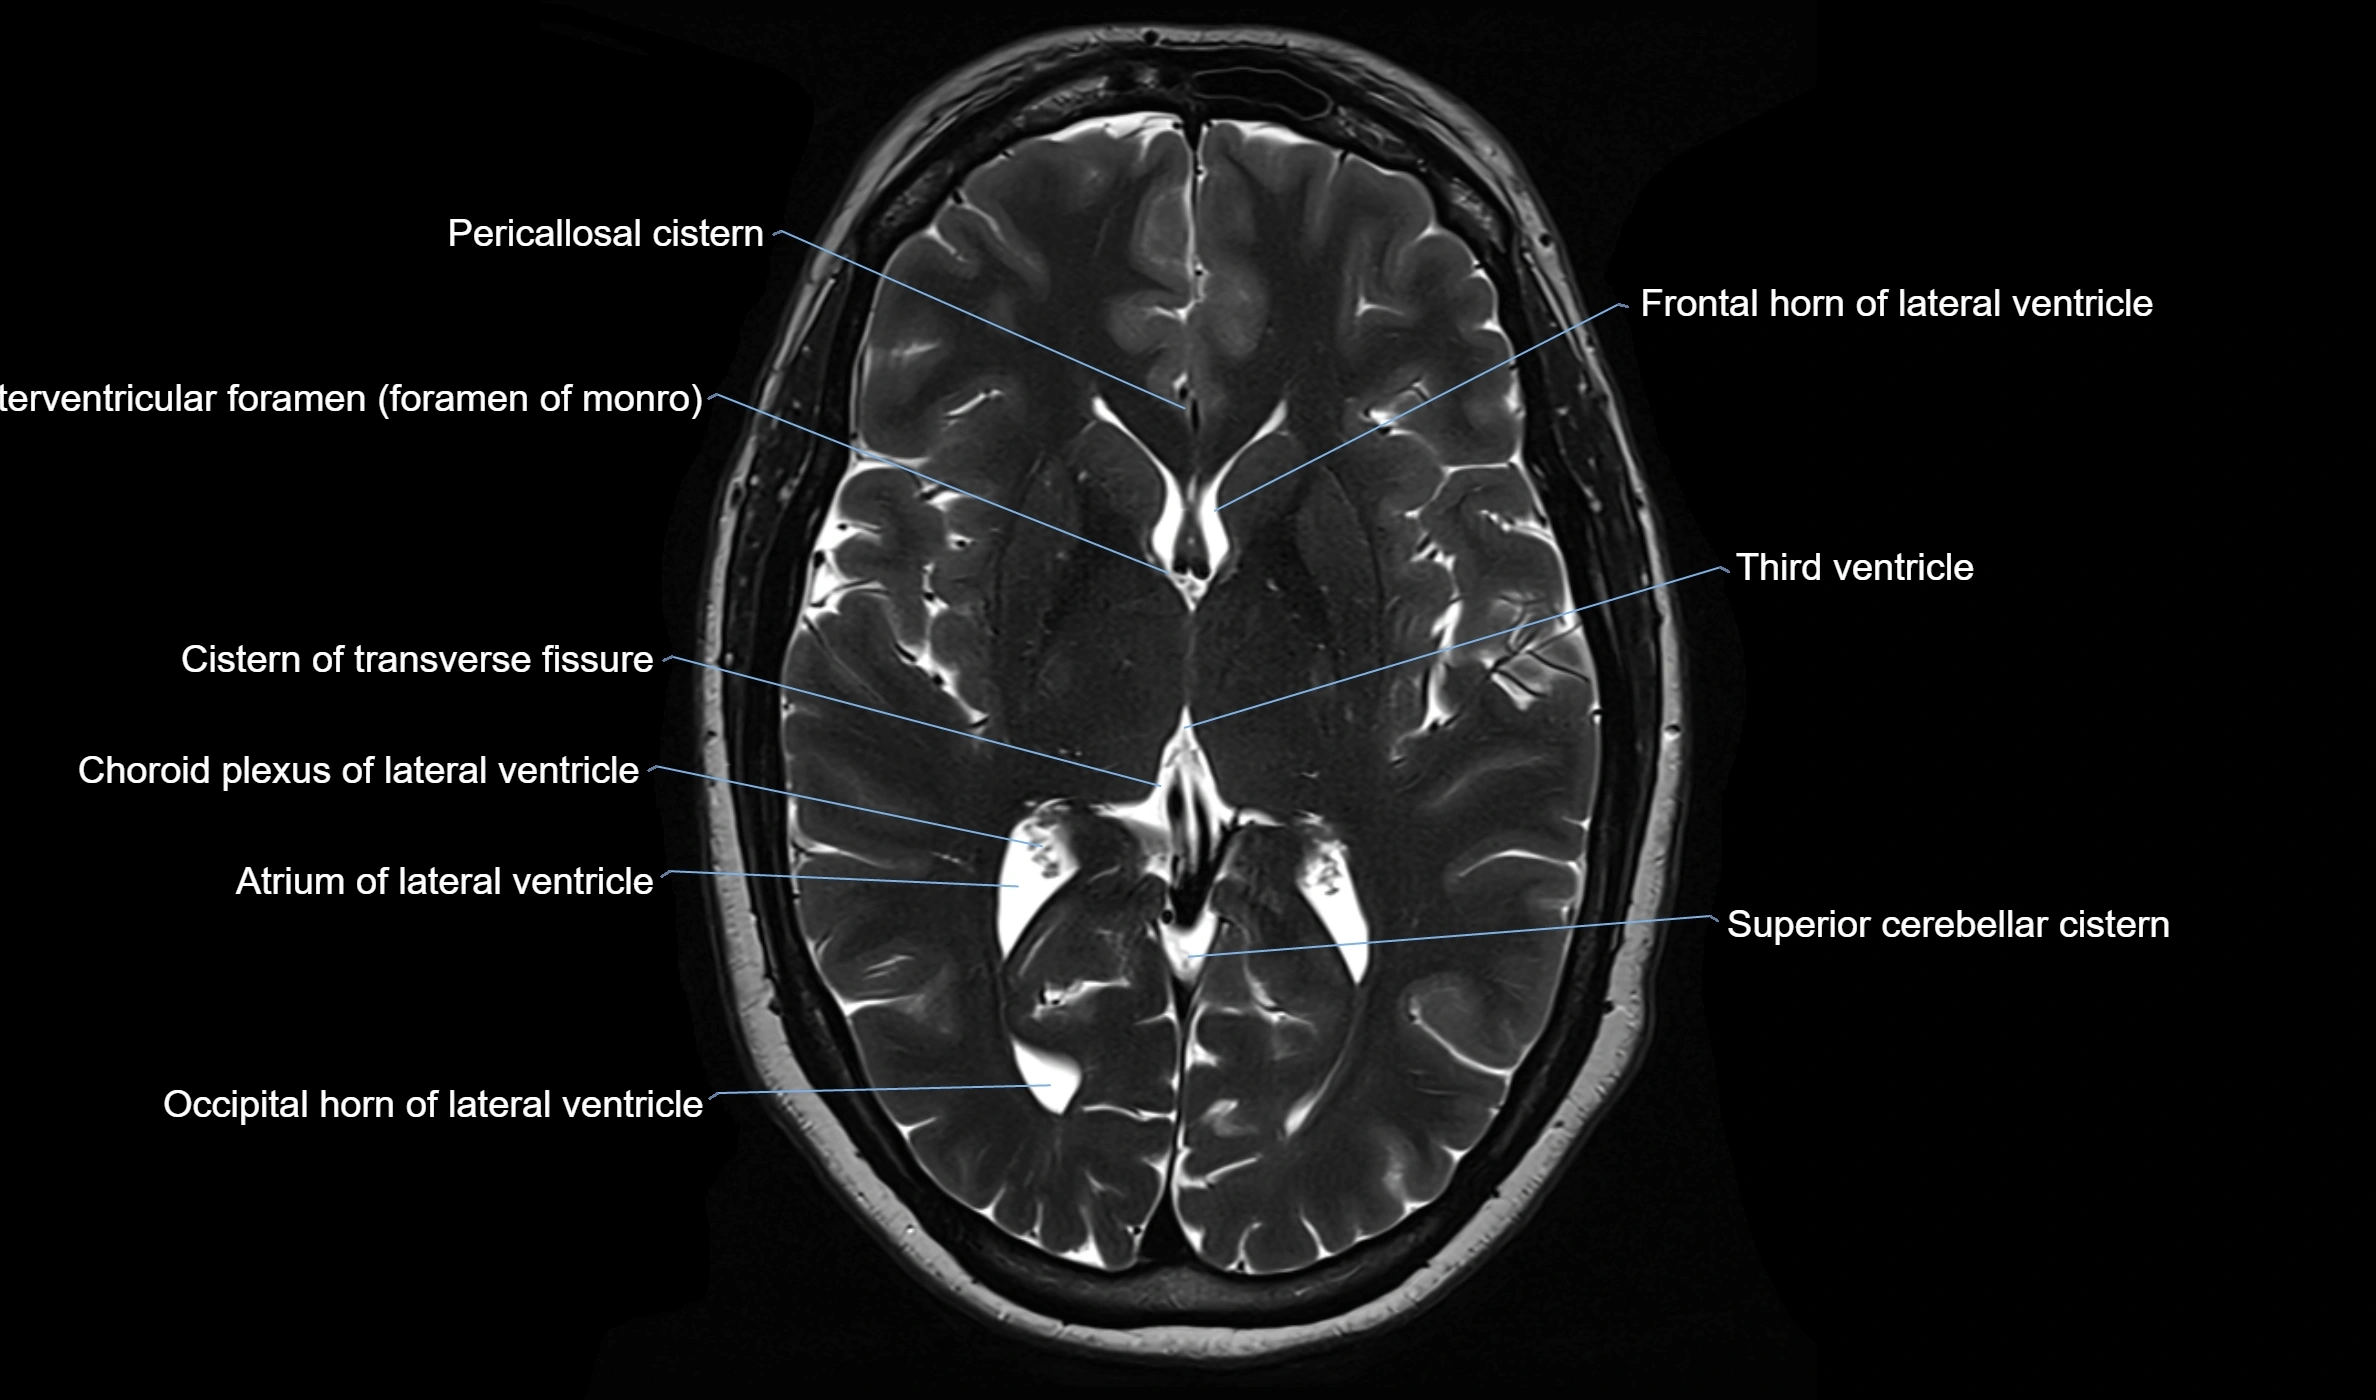

MRI images

image